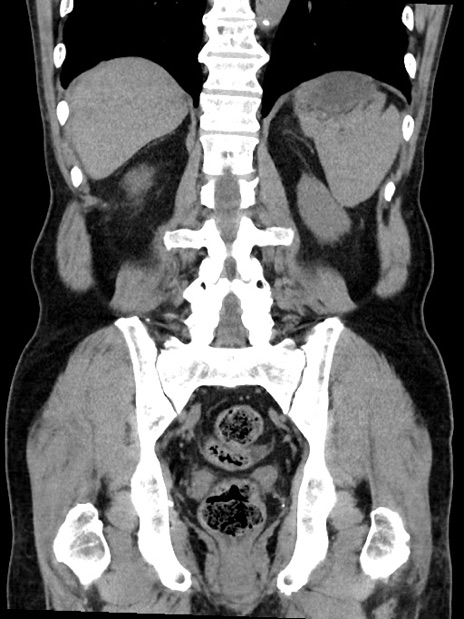

症例35(冠状断像)

【症例】70歳代 男性

【主訴】腹部膨満、嘔吐

【現病歴】昨日より腹部膨満感出現。本日増悪し、仙痛出現。嘔吐あり、受診。

【既往歴】糖尿病、胆摘後

【身体所見】BP 149/80mmHg、HR 74/min、BT 35.9℃、腹部:膨満、軟、圧痛なし。腸雑音減弱あり。上腹部正中切開瘢痕あり。

【データ】WBC 13500、CRP 1.72